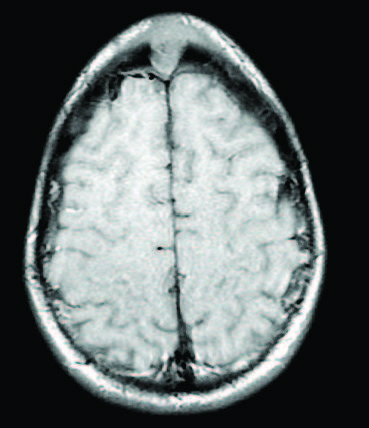

Neonatal Stroke Induced by Factor V Leiden Mutation

Lourdes Cohen, MD; Xin Ye, MD

A meconium-stained, nonvigorous girl was born at 41 weeks of gestation via normal, spontaneous vaginal delivery to a 30-year-old, gravida 1, para 1 mother.